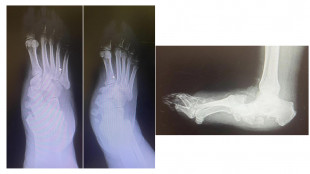

Diabete, al Gemelli soluzioni avanzate per il piede di Charcot

La rara complicanza che porta a deformità richiede complicati interventi ortopedici